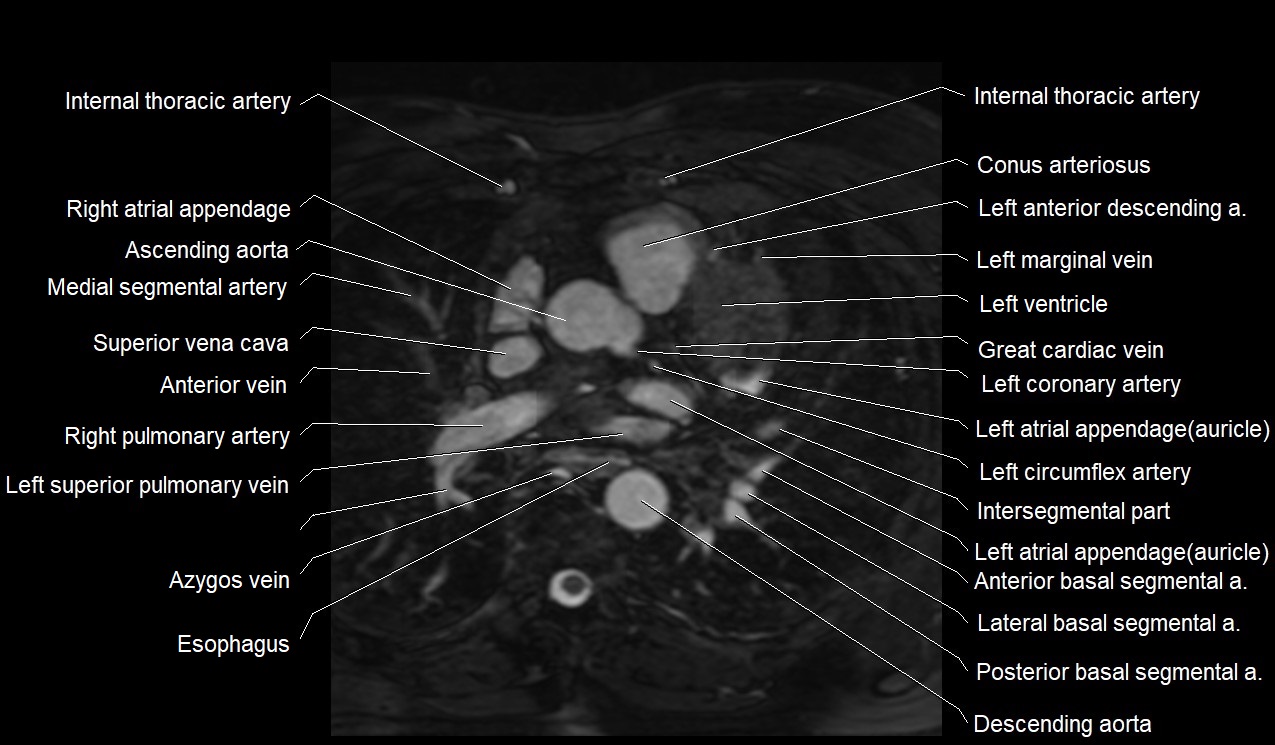

MRI image